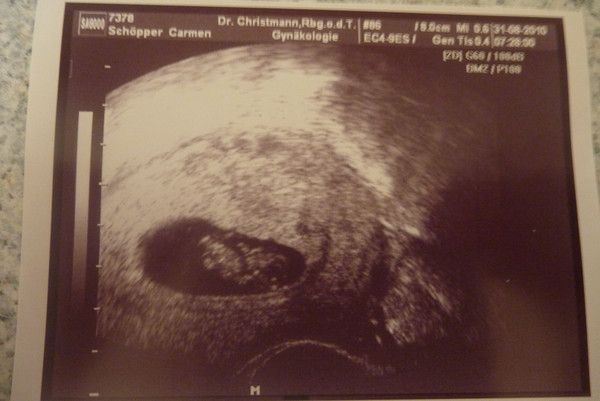

Tinchen´s Krümelchen 8.+2 SSW (9. SSW)

03.09.2010

Der Krümel ist jetzt 12,4mm groß und das kleine Herz ist auch fleißig am schlagen!!